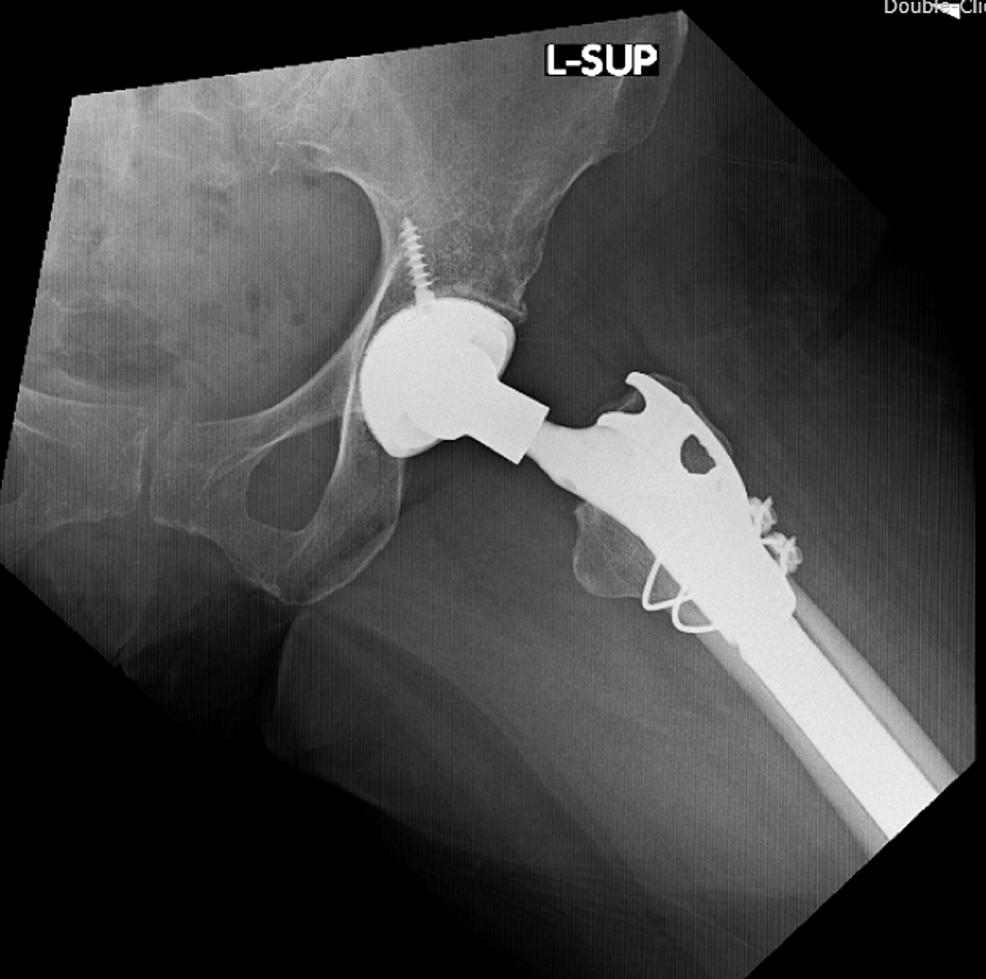

Figure 14 from Total Hip Arthroplasty With Prophylactic Fixation of Greater Trochanter and What Is A Prophylactic Fixation Several methods exist to predict the risk of pathologic fracture. prophylactic treatment before a fracture can improve patient quality of life, reduce pain scores and may reduce the. prophylactic fixation can be done in a minimally invasive fashion. prophylactic surgical stabilization is often recommended to prevent fracture rather than waiting for the. in metastatic and/or primary. What Is A Prophylactic Fixation.

Figure 1 from Total Hip Arthroplasty With Prophylactic Fixation of Greater Trochanter and Distal What Is A Prophylactic Fixation the aim is to evaluate and to highlight on value of prophylactic fixation of impending fractures in abnormal bone. prophylactic fixation can be done in a minimally invasive fashion. Several methods exist to predict the risk of pathologic fracture. Prophylactic fixation refers to operating on an impending pathologic fracture before it occurs to. It is done by inserting. What Is A Prophylactic Fixation.

Figure 2 from Total Hip Arthroplasty With Prophylactic Fixation of Greater Trochanter and Distal What Is A Prophylactic Fixation Prophylactic fixation refers to operating on an impending pathologic fracture before it occurs to. prophylactic treatment before a fracture can improve patient quality of life, reduce pain scores and may reduce the. It is done by inserting metal into the bone in order to. prophylactic fixation can be done in a minimally invasive fashion. the aim is. What Is A Prophylactic Fixation.